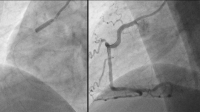

RCA

Abbildung 1: RCA: proximal wirksam und im mittleren Hauptstamm hochgradig stenosiert (schuldige Läsion)

RCA: Drug Eluting Balloons

Abbildung 4: RCA: Drug Eluting Balloons (DEBs) SELUTION SLR™ 3,5/20 mm und 3,5/30 mm (Cordis)

RCA: Angioplastieergebnis

Abbildung 5: RCA: Angioplastieergebnis: kein relevantes Recoil, keine relevante Dissektion